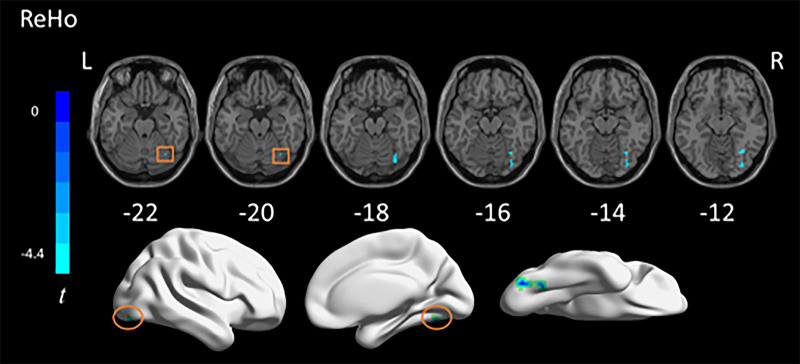

To date, most studies on autism spectrum disorder (ASD) have focused on specific age ranges, while the mechanisms underlying the entire developmental process of autism patients remain unclear. The aim of this study was to investigate the alterations in brain function in autistic individuals at different developmental stages by resting-state functional MRI (rs-fMRI). We obtained rs-fMRI data from 173 ASD and 178 typical development (TD) individuals in Autism Brain Imaging Data Exchange, spanning child, adolescent, and adult groups. We characterized local brain activity using the amplitude of low-frequency fluctuations (ALFFs), regional homogeneity (ReHo), dynamic ALFF (dALFF), and dynamic ReHo (dReHo) metrics. Pearson correlation analyses were conducted on relationships between Autism Diagnostic Observation Schedule scores and activity measures in abnormal brain regions. We found abnormal ALFF values in the medial and lateral orbitofrontal gyrus and right insula cortex with ASD compared with the TD group. In addition, compared with adolescents with ASD, we found that adults with ASD exhibited an increase in dReHo values in the posterior lateral frontal lobe. We also found that changes in ALFF were associated with the severity of autism. We found abnormal activity in multiple brain regions in individuals with autism and correlated it with clinical characteristics. Our results may provide some help for further exploring the age-related neurobiological mechanisms of ASD patients.